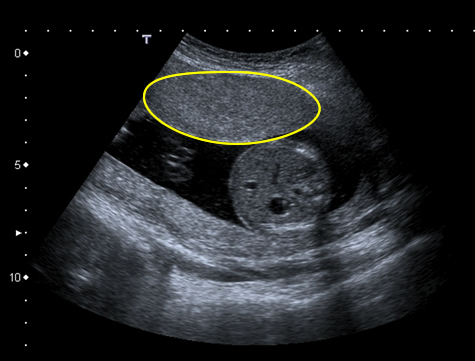

| Fig 1 Fundal placenta |